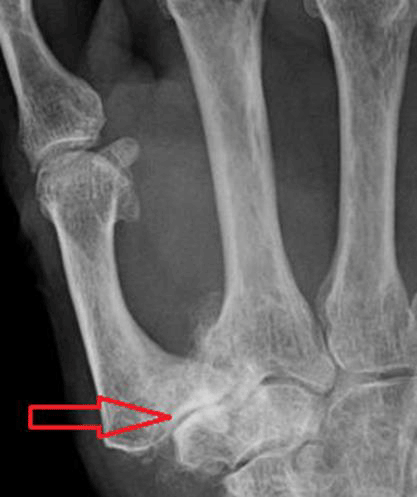

“You have arthritis of the thumb, also called osteoarthritis (OA). The problem is located where the bones of the thumb meet the wrist. The cartilage that’s normally found between the ends of these bones is disintegrating. When bone rubs bone, you can experience swelling in the area, pain and trouble moving the thumb.”

Thumb arthritis causes inflammation and degeneration of cartilage within the joint. It usually occurs at the base of the thumb where the thumb contacts the wrist. This CMC joint (carpometacarpal joint) or basilar joint allows people to open jars, turn keys or use scissors comfortably.

OA is the most common form of arthritis; it wears away the smooth, healthy cartilage located between the ends of bones. Over time, the cartilage breaks down causing bone to rub against bone leading to swelling, stiffness with limited range of motion and joint pain. Excess bone formation (osteophytes-bony spurs) can appear as part of the degenerative process

The diagnosis of OA is made by patients telling their medical story, examination of the hand by the doctor and confirmation of the diagnosis using x-rays.